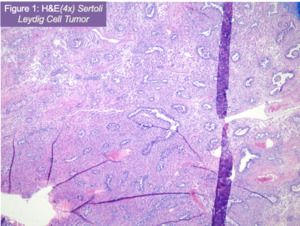

Pathologic review confirmed a poorly differentiated Sertoli-Leydig cell tumor (figure 1) of the right ovary (Stage IIIIC- pT3C Nx M0) with metastasis to the omentum and right pelvic side wall. Additionally, the right ovary was positive for high grade serous carcinoma (figure 2) metastatic from the fallopian tube. After H&E examination, immunostains for p53, napsin, PAX8, synaptophysin, CD56, and inhibin were ordered with adequate controls. Tumor cells corresponding to poorly differentiated Sertoli-Leydig tumor were positive for p53 (patchy), CD56, and inhibin (figure 3), while negative for PAX8, napsin, and synaptophysin. The metastatic high grade serous carcinoma was only positive for PAX8 and p53 (diffuse).